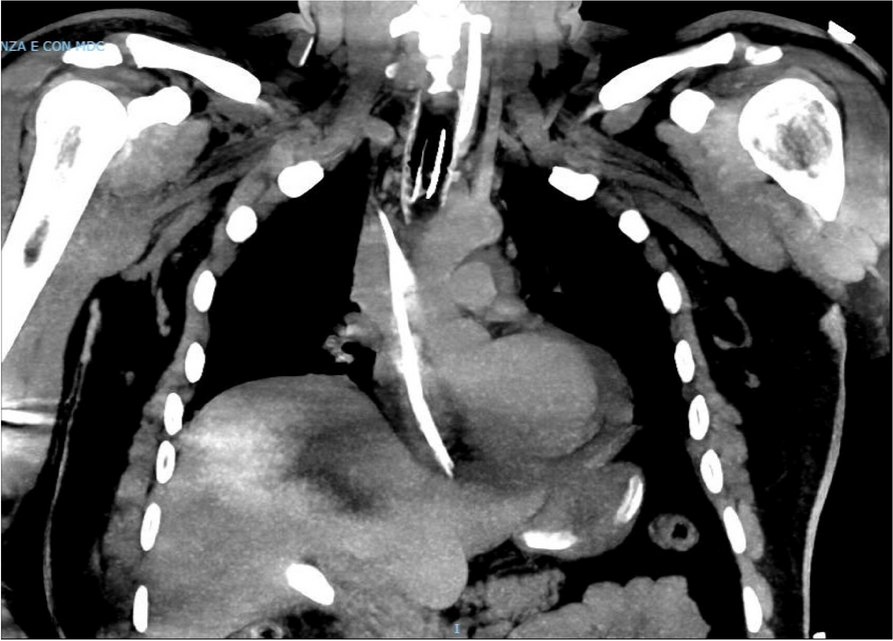

A few hours after the admission in ICU he reported a blunt abdominal pain, mainly on the right side, nausea and the exams showed increased amylase levels, urologists excluded any surgical involvement of pancreatic tissue and suspected a transient sphincter of Oddi dysfunction [3]. After one night in ICU he was transferred to the urology ward due to his clinical stability, even though Amylase peaked at 2340 U/l. Two days later abdominal pain increased to severe, with characteristics of peritonism and increased inflammatory markers. An abdomen-thorax CT scan revealed acute pancreatitis (AP) (Figure 1) and he was transferred to ICU. He started a standard treatment for acute pancreatitis and antibiotic therapy [4].

In fact, Propofol is listed as a possible cause of AP, class Ib, based on the classification of Badalov et al. [7]. Following the scheme proposed by the systematic review by Haffar et al for Propofol induced AP [6] we could confirm that our hypothesis is plausible. He satisfied the American College of Gastroenterology criteria for AP [8,9] and it is classified as severe acute pancreatitis according to the Revised Atlanta Classification with peripancreatic necrotic fluid collection [10]. Marshall score [11] after admission was two and Naranjo et al [12] probability scale for drug adverse reaction was three, meaning that the adverse reaction is possible. Latence according to Badalov et al [7] has been short or intermediate. Exclusion of other plausible causes, timing of pancreatitis symptoms and previous cases in literature support our hypothesis of propofol induced pancreatitis.

Fig. 1 (abstract A21).

See text for description